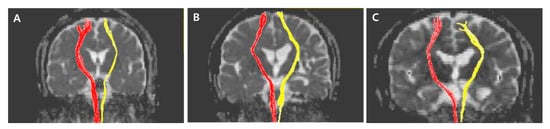

The normalized FA values of STT in the CPSP group were lower than those in the stroke control group and normal control groups; 0.79 for CPSP, 0.98 for non-CPSP, 0.98 for control (Figure 2A). The normalized FA values of STR in the CPSP group were lower than those in the stroke control group and normal control groups; 0.88 for CPSP, 1.00 for non-CPSP, 0.97 for control (Figure 2B). There were no differences in the FA values of STT and STR between the stroke control and normal control groups. The normalized FN values of STT and STR were lower in the CPSP and stroke control group than in the normal control group. However, there was no significant difference between the CPSP and stroke control for the normalized FN of STT and STR. Representative DTIs of STT in all three groups are shown in Figure 3, and those of STR in Figure 4.

Figure 3. Representative diffusion tensor tractography images of the spinothalamic tract in typical subjects from the (A) CPSP, (B) stroke control, and (C) normal control groups. The non-affected tract is shown in red, and the affected tract in yellow.

Figure 4. Representative diffusion tensor tractography images of superior thalamic radiation in typical subjects from the (A) CPSP group, (B) stroke control, and (C) normal control groups. The non-affected tract is shown in red, and the affected tract in yellow.